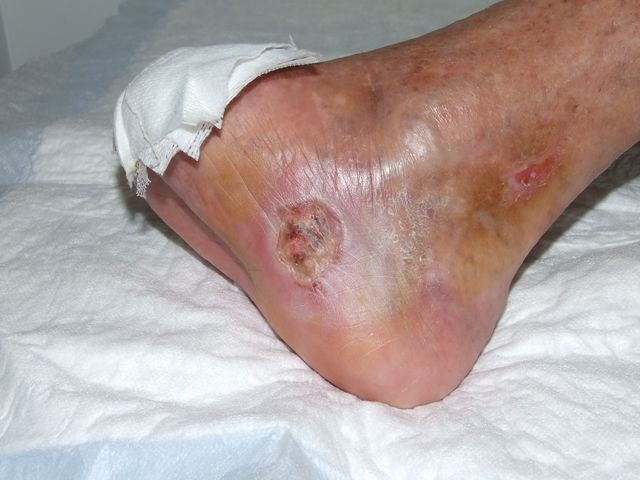

UPP 4º de talón con prominencia de calcáneo. Muy evolucionada.